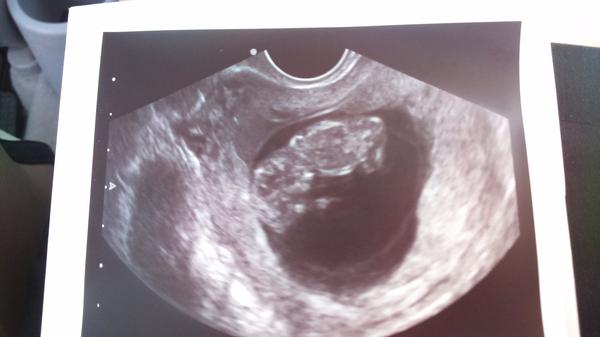

@ejuska2586 blud sak boze u lekara na potvrdene tehu davala sem sono 26.4 je tam 6plus5 je tam ciernobielom tak 29.maja by mala byt 11 plus 2 dni ako si vysvetlis to sono z 26.4 ze tam je plus5 a nerobte z lekarov idiotov sak to aj student mediciny vie pocitat tehu dni a nie lekar ktory ma denodennu prax a som skoncila....

@ejuska2586 a ako je mozne ze 16 maja bola 9plus4 to by sedelo podla toho sona z 26.4 co sme davala....tak uz ma to nebavi stale sa tu nejake spekulacie .prve sono dala 26.4 bola 6plus5 ......

@archanjel007 no ja už vôbec tomu nechápem no neráta sono tt podľa veľkosti plodu? Veď na obrazovke to tam píše že 6+4 tt či nie?

@matka295 rata podla velkosti plodu ja ked som bola tiez som bola tak a to mi 3 tyzdne meskala menses poslednu som mala 15.12 a u lekara som bola 6 aprila a bola som 6plus4 a bilo nam srdiecko🙂